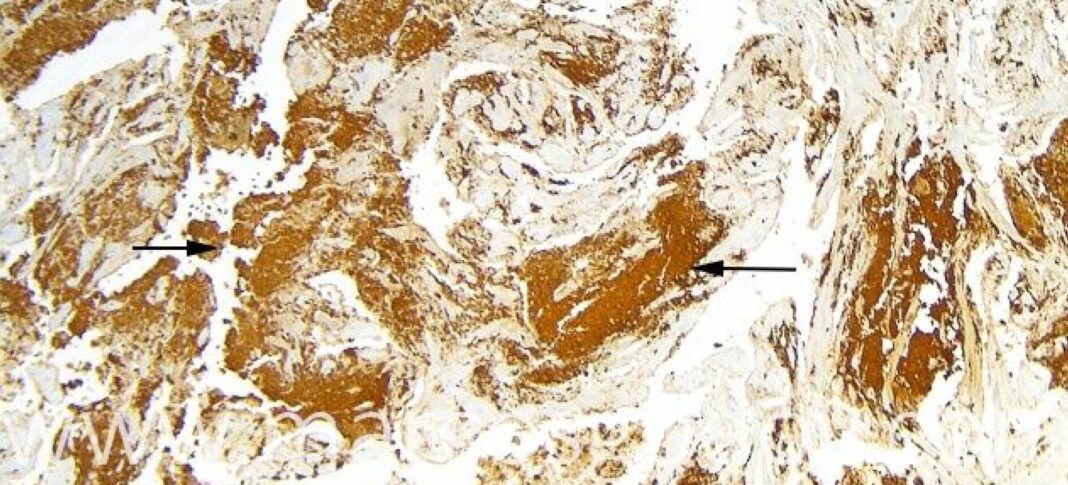

Bajo el título «Enfermedad bacteriana del riñón (BKD): Consideraciones para la prevención y control», el Dr. Godoy expuso sobre la relevancia de esta patología en la mortalidad de salmónidos, como asimismo el conocimiento que se tiene de la enfermedad.

«EL BKD representa un porcentaje no menor, específicamente, de las causas infecciosas de mortalidad. Por ejemplo en trucha y salmón del Atlántico representa alrededor de un 8% del total de mortalidades específicas infecciosas. Sin embargo, esta enfermedad en salmón Coho, representa el 26% de las mortalidades de causas infecciosas. Por lo tanto, el BKD es uno de los actores importantes de la etiología, de las enfermedades, en nuestro país», argumento el investigador.